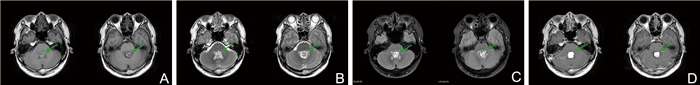

小脑认知情感综合征1例报告并文献复习

姚红艳, 唐莲, 王倩, 张玉梅

2026, 24(2): 350-353. doi: 10.16766/j.cnki.issn.1674-4152.004395

6 0

摘要:

临床上小脑损伤患者会出现认知功能障碍及情感调节障碍,临床表现轻于大脑受损所致的认知障碍,在实际工作中易被忽略。本文报道1例血管母细胞瘤患者因出现小脑或其环路受损导致出现轻度认知功能障碍及情感调节障碍的病例,患者男性,43岁,因“行走不稳3个月、反应减慢、焦虑、视物异常1.5个月”入院,入院后完善认知心理学测评等相关检查,最终诊断为“很可能的小脑认知情感综合征”;经过个体化的功能康复,患者症状均较前改善。本文对该病例进行报道,以期为临床上小脑认知情感综合征的诊断及治疗提供参考。